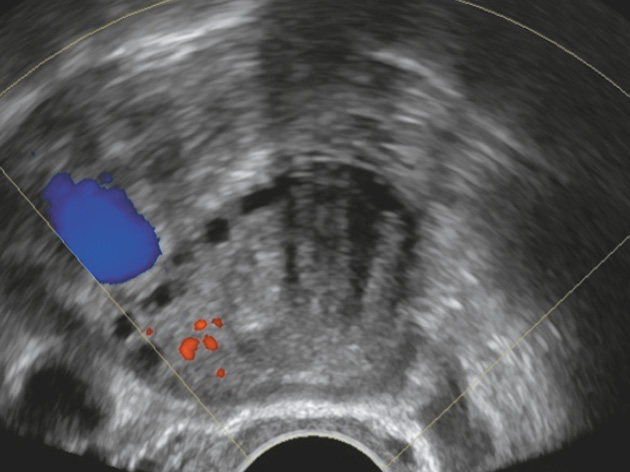

Клинический пример (рис. 9)

Рис. 9. Оценка новообразования у пациентки Н., 60 лет

Fig. 9. Evaluation of neoplasm in patient N., 60 years old